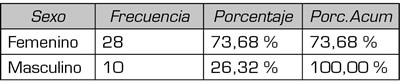

Se identificaron 45 pacientes llevados a bloqueo de nervios cluneales con diagnóstico de dolor lumbar crónico con signos y/o síntomas de clunealgía, cumpliendo los criterios de inclusión. Los síntomas más frecuentes fueron el dolor neuropático irradiado a miembros inferiores en el 57 % (n = 21) y el dolor lumbar en el 36 % (n = 13) se obtuvieron datos sociodemográficos descritos en Tabla I y II. Hubo pérdida de seguimiento de 11 pacientes posterior al procedimiento (Figura 2).

Tabla I. Variables sociodemográficas.

Tabla II. Variables sociodemográficas.

La edad de incidencia de clunealgía reportada en diferentes estudios esta entre 50 a 68 años (2,15), lo cual se puede apoyar con nuestro estudio cuya mediana de edad fue 54 años. Por otro lado, la población femenina en nuestro estudio representó el 73 %; es un reflejo de la afectación del género, en forma frecuente, y en concordancia con lo encontrado por 2013 Kuniya y cols., con un 54 % (16).